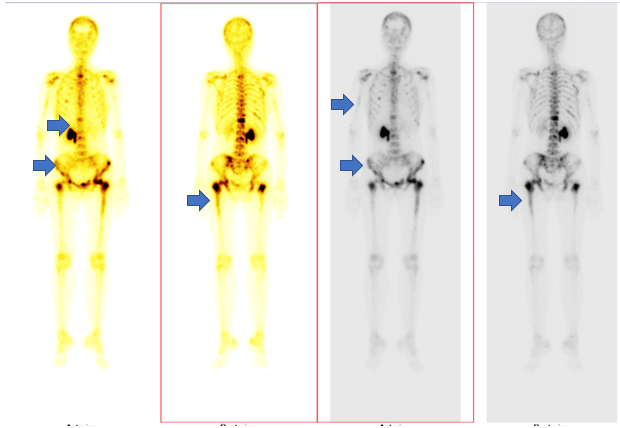

– Xạ hình xương: Hình ảnh tăng hoạt tính phóng xạ nhiều vị trí xương hộp sọ, nhiều đốt sống, xương cùng, xương cụt, nhiều xương sườn, xương cánh tay hai bên, xương chậu hai bên, xương đùi hai bên.

Hình 7. Hình ảnh di căn xương đa ổ trên xạ hình xương (các mũi tên màu xanh)